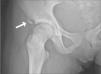

Caso 2Niña de 12 años coinfectada verticalmente por el VIH y virus de la hepatitis C (VHC) estadio A2 (nadir CD4 del 27%). Inició TARGA en 1999: azidotimidina (AZT) + 3TC + IDV. En 2002, por fallo terapéutico cambió a d4T + ddI + EFV. En 2005, tras constatar escasa recuperación inmune y guiados por el test de resistencia, se modificó a LPV/r + ABC + 3TC, tratamiento que se mantiene en la actualidad. En 2006, tras pegarle una patada a un balón, cayó al suelo. En la radiografía de cadera se objetivó arrancamiento de la espina ilíaca anteroinferior (fig. 2). En el momento de la fractura ósea la paciente presentaba buen estado nutricional y sin menarquia, CD4 de 379 (23 %), CV de 4.078 copias/ml (3,61 log), ácido láctico, hormonas tiroideas, perfil hepatorrenal, desoxipiridinolina, 1,25-dihidroxi-vitamina D, 25-hidroxi-vitamina D, hormona paratiroidea (PTH) y osteocalcina normales. La fosfatasa alcalina ósea era de 90,86μg/l. Densitometría femoral por rayos X: T score −1,5 y de columna lumbar: T score −1,9. Conversión a valores de referencia de Z score: normales. Tratamiento: reposo hasta conseguir la recuperación. Diagnóstico: fractura patológica sin osteopenia secundaria a VIH-VHC y TARGA.

El caso 2 es el de una adolescente con fractura patológica de cadera tras un traumatismo mínimo, con marcadores de remodelación ósea, función tiroidea, perfil hepatorrenal y estado nutricional normales. Cualquiera de ellos si hubiese estado presente, podría haber sido responsable de la fractura. La etiología de estas alteraciones es multifactorial y pueden intervenir la propia infección del VIH, el tratamiento antirretroviral y factores generales como la malnutrición, hipogonadismo, etc.5,26. En niños y adolescentes infectados por el VIH con TARGA se ha demostrado que no se alcanza un adecuado pico de masa ósea10. En nuestro caso, la densitometría de cabeza y cuello femoral estaban dentro del rango de la normalidad, por lo que se desestimó el tratamiento con bifosfonatos, que es el único tratamiento posiblemente eficaz en casos de osteopenia. Posiblemente, la infección por el VIH en una niña cercana a la pubertad o incluso la coinfección con el VHC puedan haber desempeñado un papel en la patogenia de la fractura18,27.